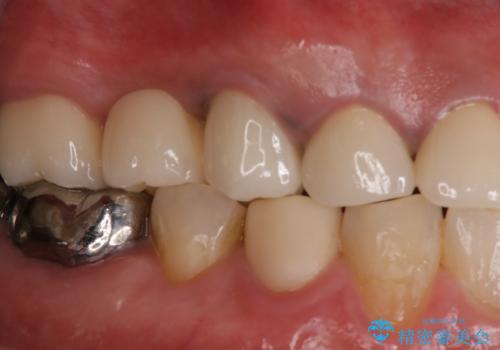

歯肉からの出血 適合の悪い銀歯をオールセラミックのブリッジにやり替え

以前の被せ物を除去し、仮歯に変えてすぐに異和感がとれました。

歯周治療を行い、歯肉が引き締まってから補綴治療しました。